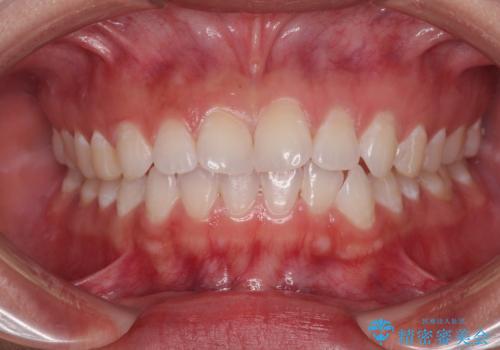

- ソーシャルメディアでのゲームに夢中になっている最中に車と接触し、前歯の抜歯を余儀なくされた患者様です。

初診時では前歯が保存できる可能性も模索しましたが、損傷が激しく3歯を抜去することとなりました。

保存となった隣在歯も神経が失活していており、補綴治療が必要であったので、オールセラミッククラウンにて補綴治療することとしました。

奥歯には元々欠損があり、欠損に伴う咬合不正も認められたため、部分矯正を行った上でインプラント補綴治療も行うこととしました。